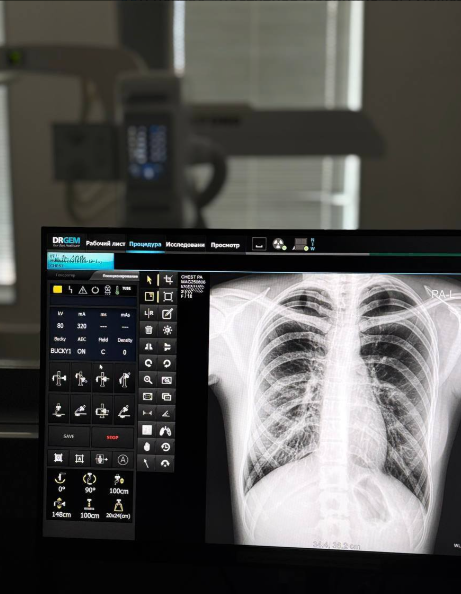

Как часто нужно делать флюорографию или рентген лёгких?

Флюорография — простой, быстрый и доступный способ проверить состояние лёгких. Она помогает вовремя выявить туберкулёз, воспаления и даже новообразования. Как часто проходить обследование:

Флюорография — простой, быстрый и доступный способ проверить состояние лёгких. Она помогает вовремя выявить туберкулёз, воспаления и даже новообразования.